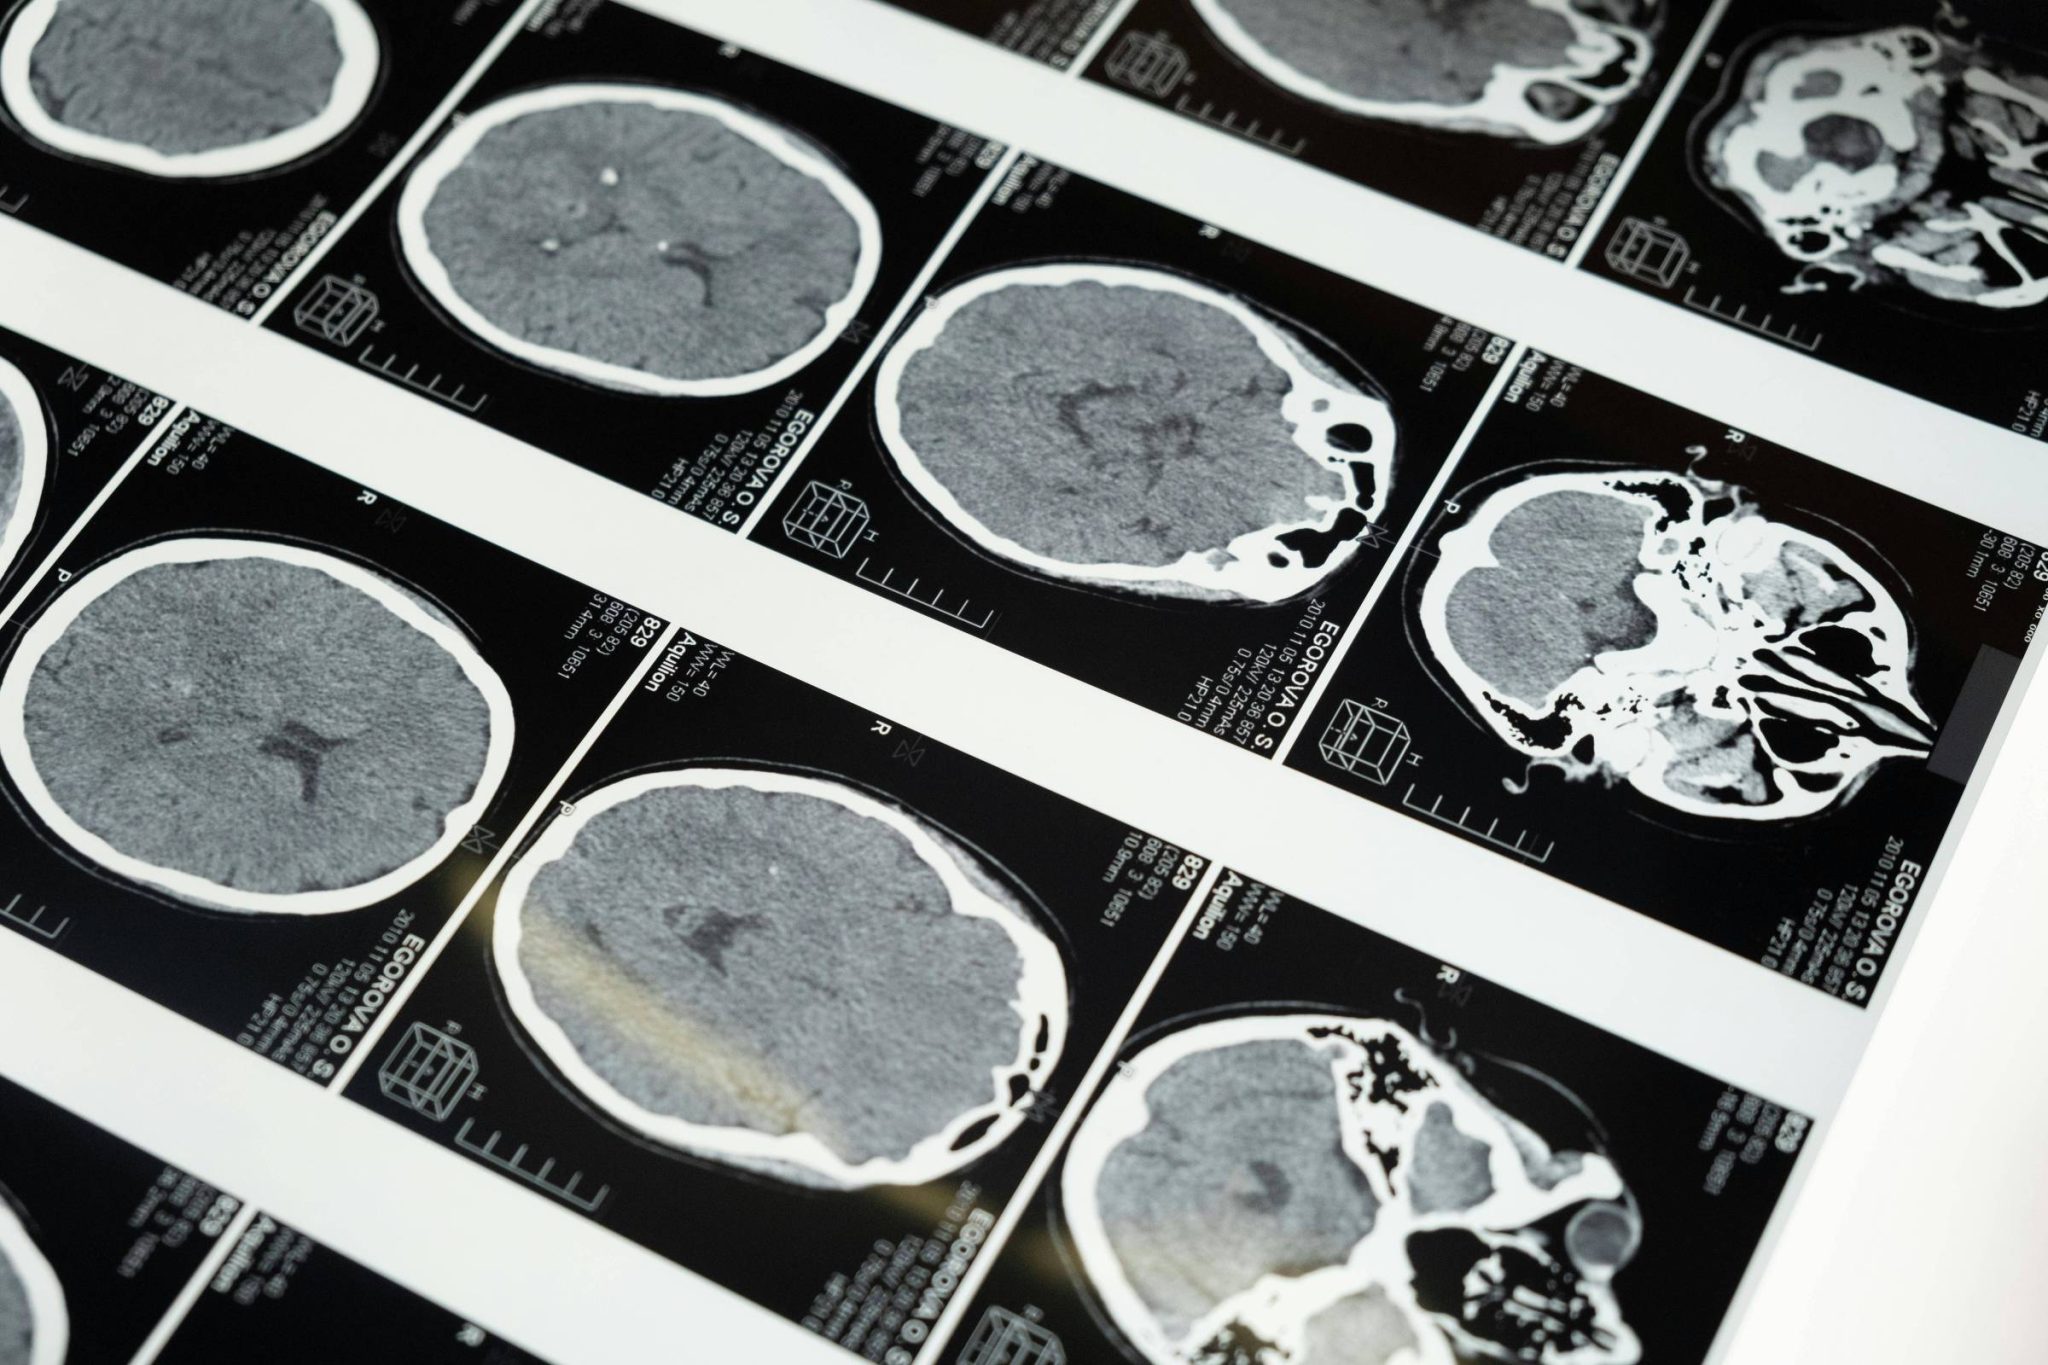

A Anvisa (Agência Nacional de Vigilância Sanitária) aprovou o Kisunla (donanemabe) primeiro medicamento destinado exclusivamente para o tratamento de Alzheimer na última terça-feira (22). Com características de atuação biológica, o fármaco fabricado pela Eli Lilly não trata os sintomas motores da doença, como perda de memória, desorientação, mudanças na personalidade e comportamento, mas pode ajudar no atraso da progressão da doença.